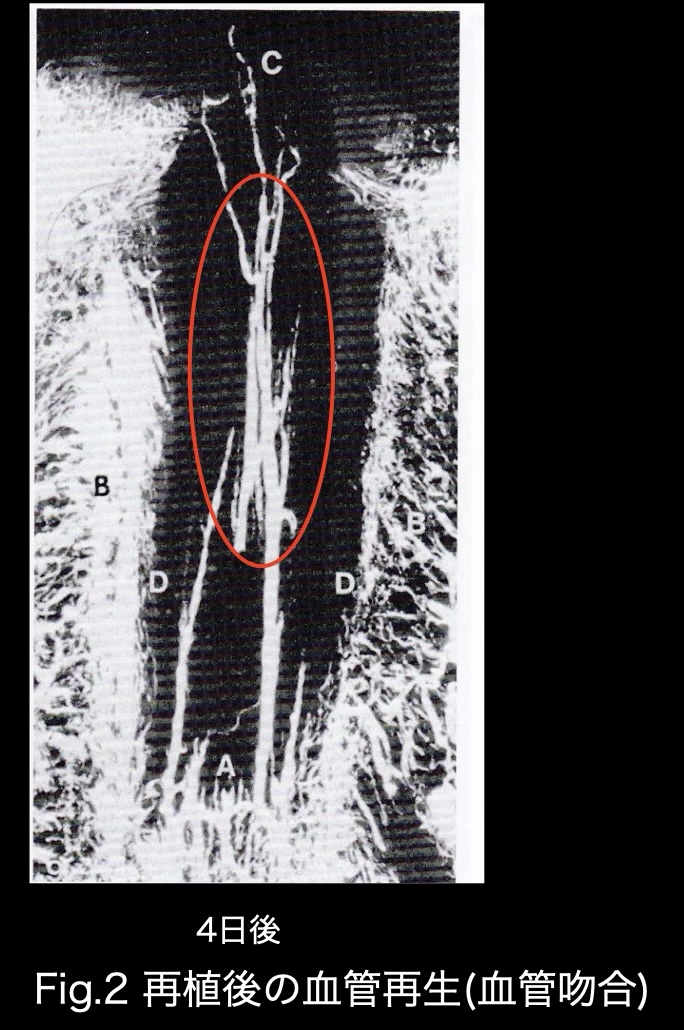

Fig.2は別の再植後の結果になります。再植後4日目に歯髄の先端部に数本の細い血管が見られます。さらに歯の頭の部分まで(冠状歯髄)走る太い血管が数本見られます(Fig.2赤丸印)。これは再生された血管がつながった状態、つまり血管吻合を表しています。Skoglundらによって血管の再生が確認され、後の”Revascularization”の臨床応用に大きな影響を与えた研究だと言えます。